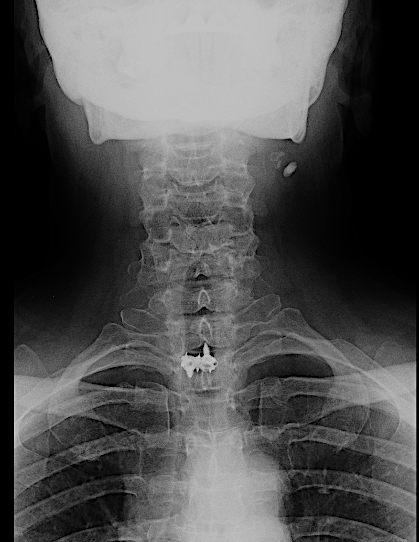

RX AP control postoperatoria.

Obsérvese, en la imagen anterior, la incisión usada en relación con la prótesis. No fue necesario realizar ninguna esternotomía (aunque el cirujano torácico estaba avisado). Para mejorar la visión sí que se resecó parte del platillo inferoanterior de Th1.

La caja atornillada no planteó tantas dificultades como la descompresión.

Difícilmente se aprecia la prótesis

Copia con marcaje de los tornillos de la misma

En las RX lateral de control no se aprecia bien la caja atornillada, sin embargo, la paciente mejoró la clínica álgica y mostró recuperación funcional en MSD en los controles, por lo que decidí esperar a los 6 meses para la RM cervical.